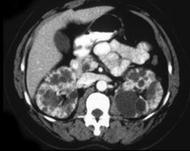

问题 女,35岁,无特殊临床表现,请根据CT图像,选择最可能诊断 ( )

选项 A、囊性肾癌 B、单纯性肾囊肿 C、多发性肾囊肿 D、复杂性肾囊肿 E、多囊肾

答案 E